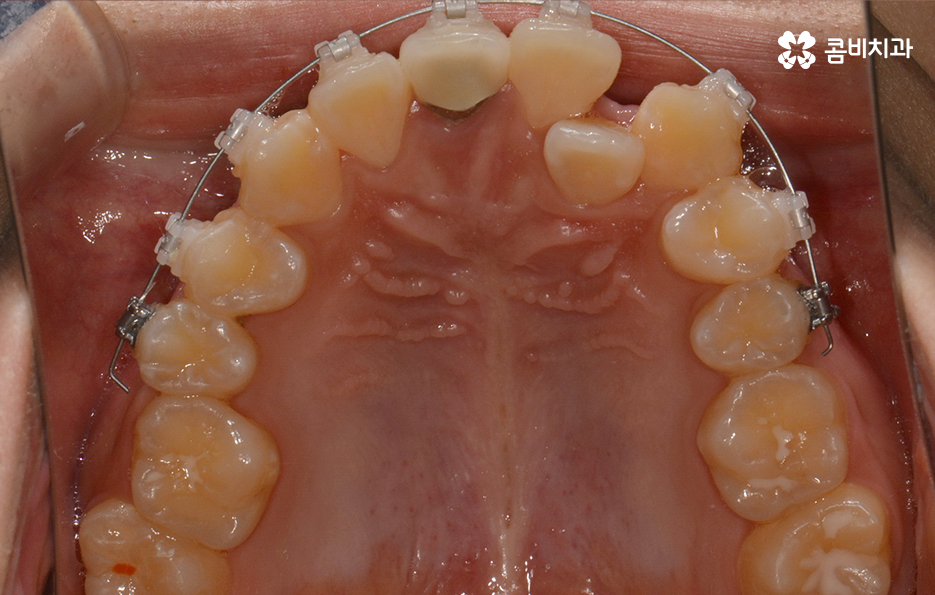

왼쪽이 윗니이고 오른쪽이 아랫니인데 치열의 불규칙함이

심한 편이다 보니 평소 음식물이나 치석이 끼기 쉬운 환경이

되고 이러한 구강 환경이 지속된다면 충치와 잇몸질환의 발생률이 높아질 수 있어요.